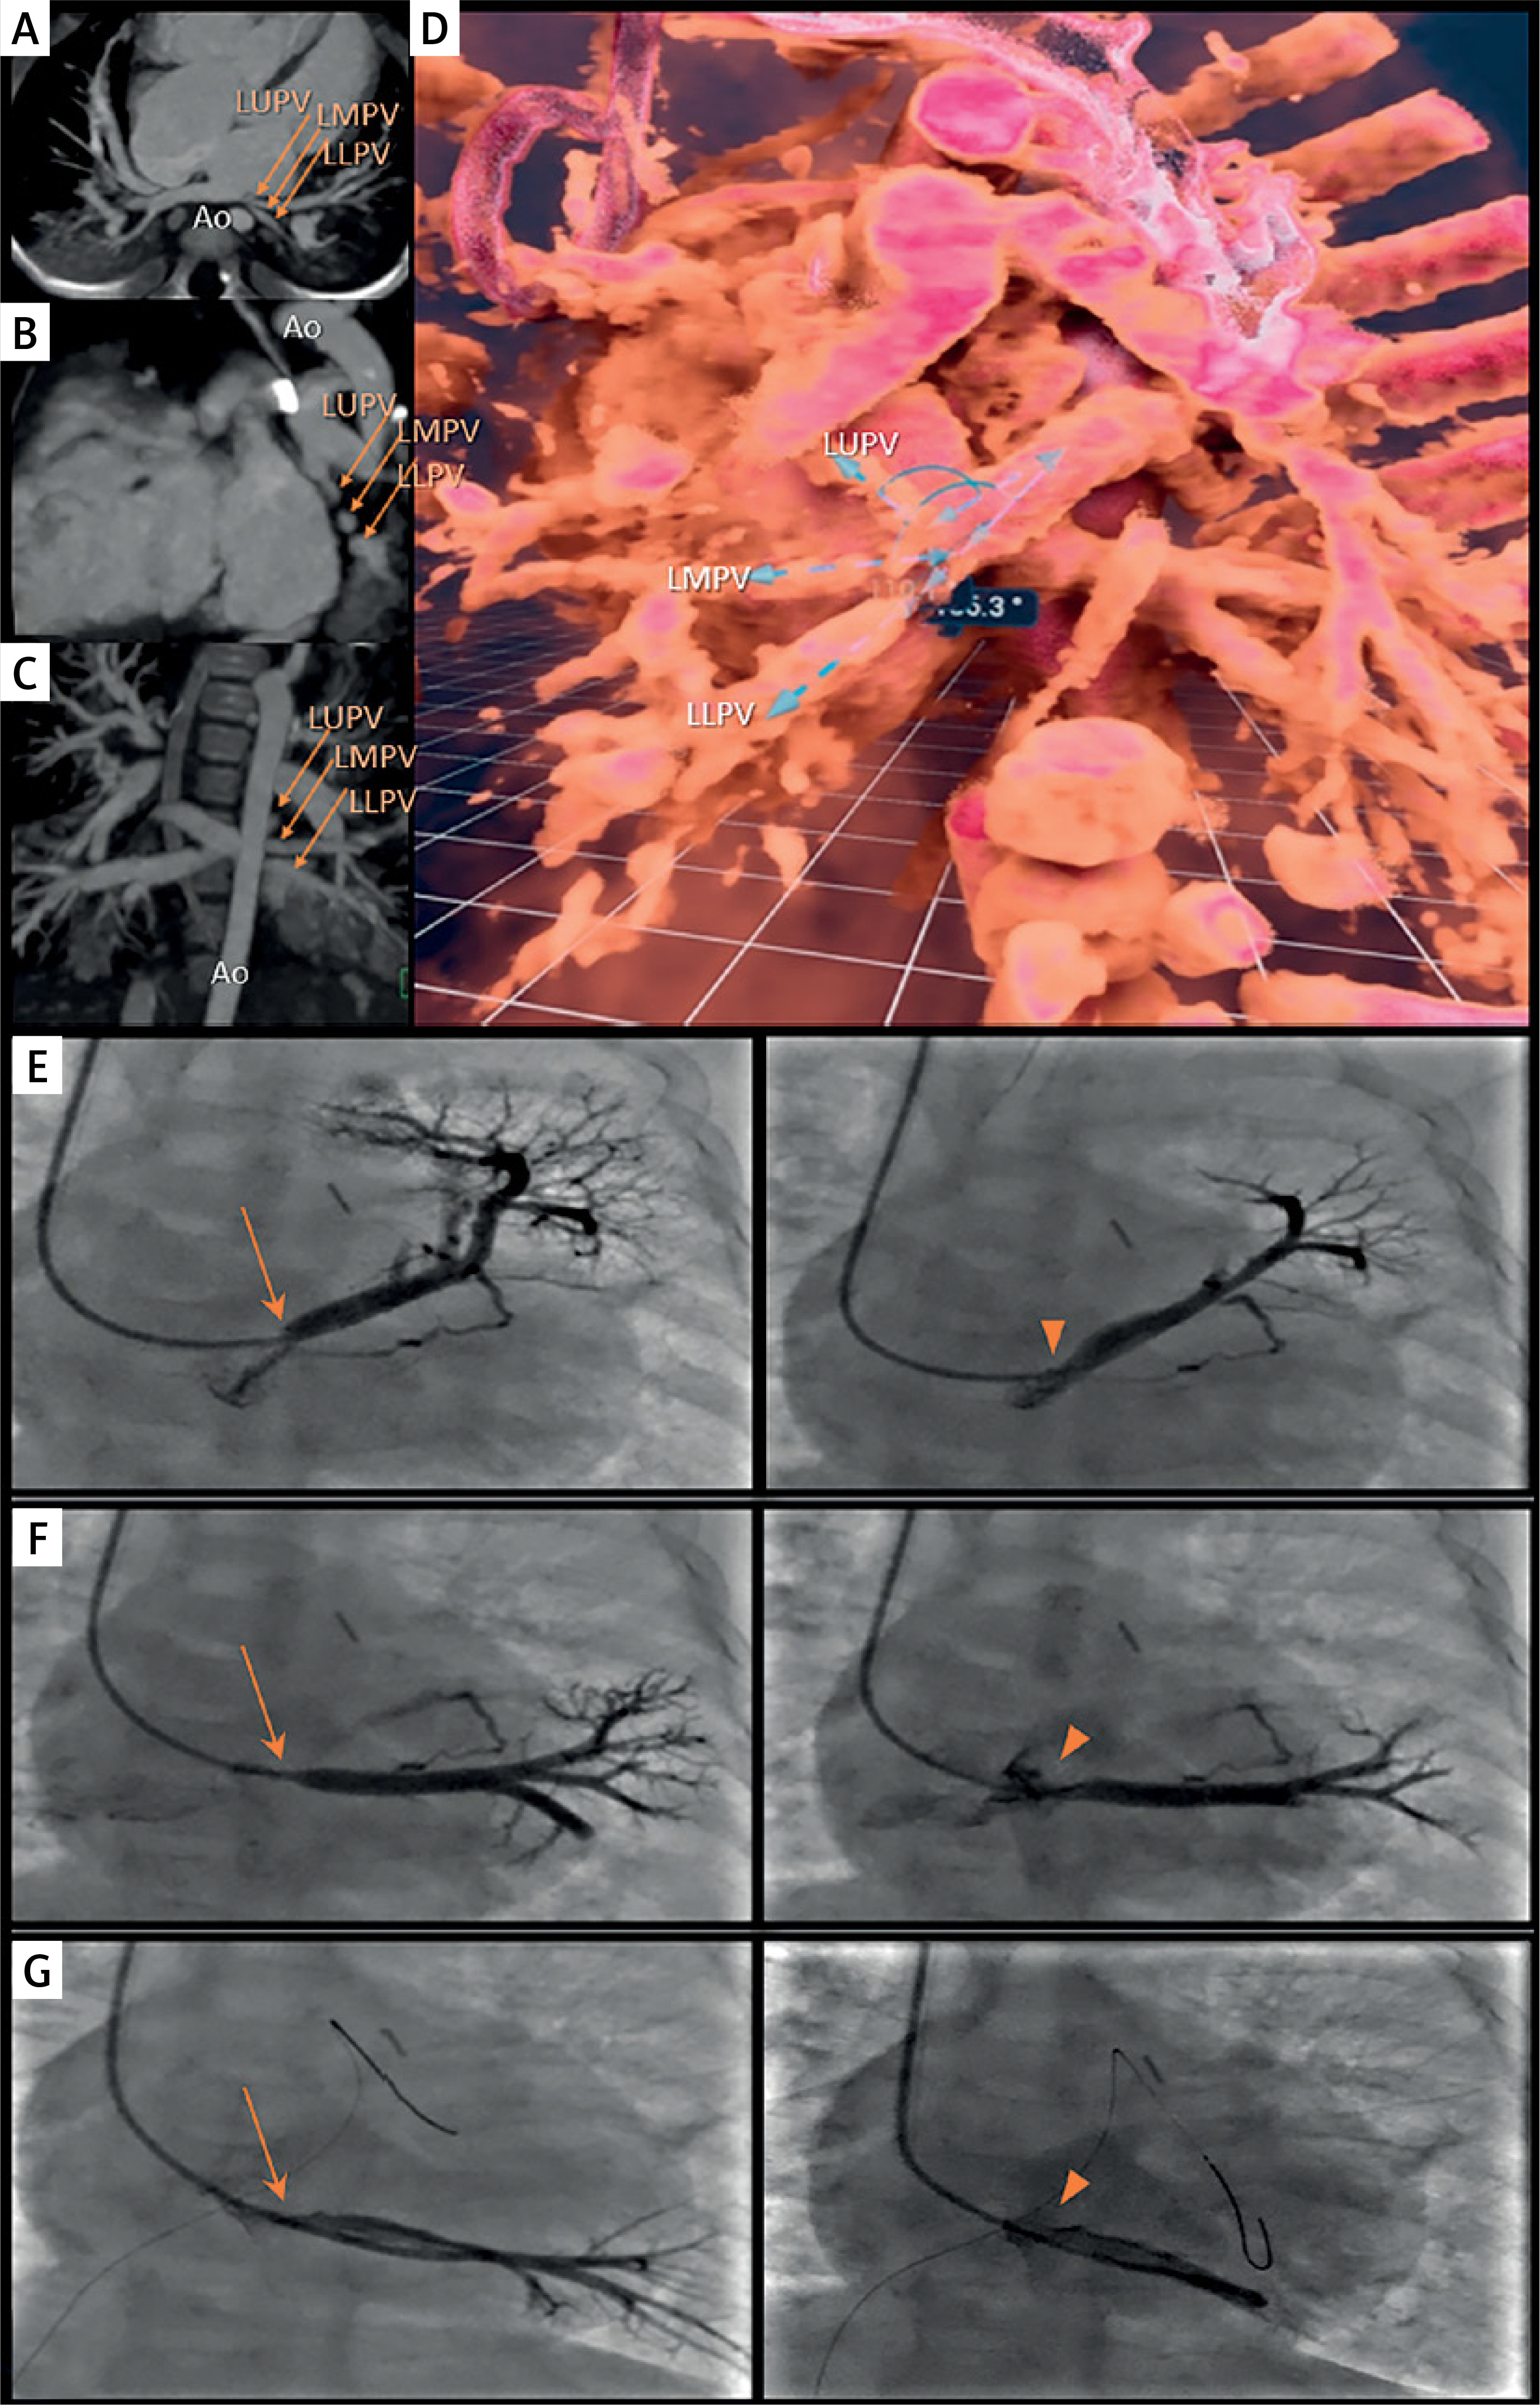

At 7 months of age (5.4 kg), LPV re-stenosis was noted by echocardiography with a mean gradient of 5 mm Hg. Repeat CT showed re-stenosis of the 3 LPVs, located in close proximity to the aorta (Figures 1 A–C). The CT-based VR model (Vmersive, VR-learning, Poland; Figure 1 D) allowed precise spatial planning of the catheterization, including access from the SVC. All 3 stenosed LPV were successfully identified, and effective angioplasty was performed using a combination of balloon catheters with diameters of 4, 5, and 6 mm (Ryujin, NC Emerge), with reduction of mean gradients from 11 mm Hg to 1 mm Hg, measured in the LUPV and middle LPV (Figures 1 E–G). The follow-up echocardiogram demonstrated trivial LPV flow turbulence with a 2 mm Hg mean gradient.

Figure 1

Multimodal imaging (CT, VR, 2D angiography) in the diagnostic and therapeutic process of patient 1. A – Axial view, B – sagittal view, C – coronal view of the CT scan. Arrows indicate the left upper pulmonary vein (LUPV), left middle pulmonary vein (LMPV), and left lower pulmonary vein (LLPV), respectively. The course of the vessels is shown in close proximity to the aorta (Ao). D – Virtual reality reconstruction, posterior view. The three narrowed left-sided pulmonary veins (upper – LUPV, middle – LMPV, and lower – LLPV) are shown from the back. Blue dashed arrows indicate the course and spatial arrangement of the vessels. E – Left image: Initial angiography, contrast injection into the left upper pulmonary vein (LUPV). Significant stenosis is visible, indicated by an orange arrow. Right image: Final angiography post-interventional procedure. The dilated stenotic segment is visible, indicated by an orange arrowhead. F – Left image: Initial angiography, contrast injection into the left middle pulmonary vein (LMPV). Significant stenosis is visible, indicated by an orange arrow. Right image: Final angiography post-interventional procedure. The dilated stenotic segment is visible, indicated by an orange arrowhead. G – Left image: Initial angiography, contrast injection into the left lower pulmonary vein (LLPV). Significant stenosis is visible, indicated by an orange arrow. Right image: Final angiography post-interventional procedure. The dilated stenotic segment is visible, indicated by an orange arrowhead